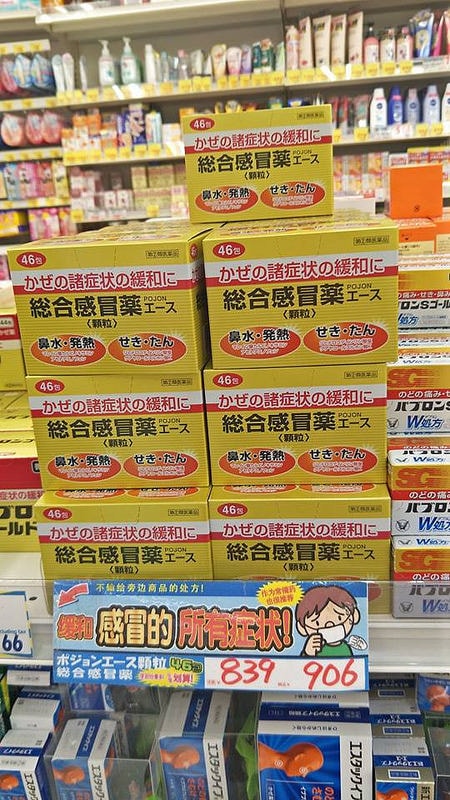

比起新LULU A

我媽更愛這一款葛根湯的顆粒

每次去日本都會叫我幫她多買幾盒

對於提早預防感冒她覺得很有效

但因為我不愛藥粉狀的任何東西

請不要問我吃起來感覺怎樣

我就是覺得有點苦啊><